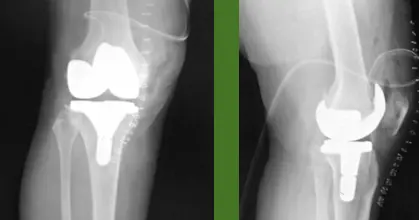

- ✓ Prosthetic joint

- Two weeks before planned Arthroplasty